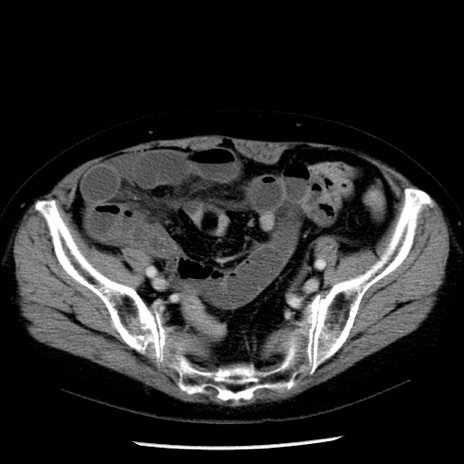

症例13(横断像)

【症例】70歳代女性

【主訴】腹痛、嘔吐

【現病歴】15時間程前(昨晩)より腹痛あり。今朝になっても症状の改善なく、嘔吐あり。腹痛も増悪あり、救急外来受診。

【既往歴】子宮癌全摘術後

【身体所見】意識清明、BP 121/72mmHg、P 74bpm、SpO2 100%(RA)、腹部:平坦・軟、腸雑音ほぼ聴取せず。下腹部・心窩部・臍左上に圧痛あり。反跳痛なし。

【データ】WBC 10600、CRP 0.15